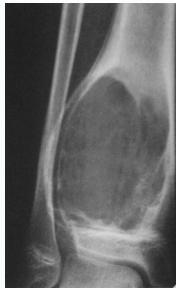

Aneurysmal Bone Cyst

- Child - young adult

- Metaphysis of long bone

- X-ray:

- Well-defined cyst

- Trabeculated

- Eccentrically placed

- Ballooning

- Bloody content

- Treatment:

- Curettage and bone graft

- Metaphysis, Eccentric

Comparison of Cyst-Like Lesions in Bone

- At metaphyseal side of physis

- Expansile